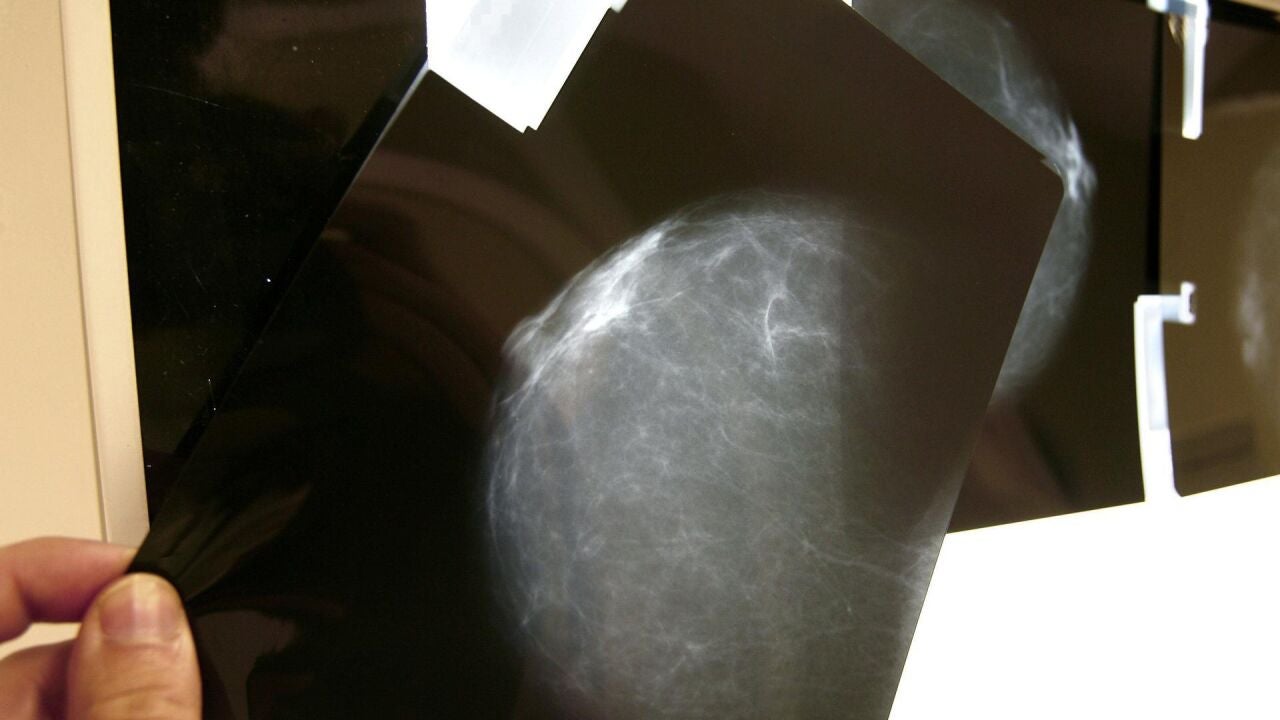

La melatonina inhibe la formación de nuevos vasos sanguíneos en tumores de cáncer de mama

La melatonina, una hormona que segrega el cerebro y que regula, entre otros procesos, el reloj biológico del organismo, tiene un efecto inhibidor en la angiogénesis (formación de vasos sanguíneos nuevos) tumoral en cáncer de mama.

Así lo confirman los primeros resultados de un estudio sobre la relación entre la melatonina y la angiogénesis en el cáncer mamario que investigadores de IBIMA Plataforma Bionand han publicado en la revista Biomed Pharmacother.

Este proyecto, que cuenta con la colaboración de la Fundación Unicaja y se desarrolla en los hospitales universitarios Regional de Málaga y Virgen de la Victoria, además de en la Universidad de Málaga (UMA), abre nuevas perspectivas para potenciales líneas de investigación contra el cáncer.

La melatonina, una molécula con propiedades antitumorales en el cáncer de mama, ha sido identificada como un inhibidor del factor de crecimiento endotelial vascular (VEGF). La inhibición del VEGF es crucial para prevenir la formación de nuevos vasos sanguíneos en los tumores, un proceso conocido como angiogénesis tumoral, que promueve el crecimiento y la propagación del cáncer.

El objetivo de este estudio, liderado por la profesora de la UMA e investigadora de IBIMA Plataforma BIONAND Maribel Queipo, ha sido desarrollar ensayos innovadores para evaluar los efectos antiangiogénicos de la melatonina. Para ello se han utilizado ensayos in vivo en membrana corioalantoidea de pollo (ensayos CAM) y un modelo in vitro 3D con esferoides de células endoteliales.

La conclusión de los investigadores es que la melatonina ejerce un efecto inhibidor significativo sobre la angiogénesis tumoral inducida por VEGF y células de cáncer de mama MCF-7.

Los resultados, afirman los expertos, ponen de manifiesto la necesidad de continuar estudiando en el desarrollo de nuevos enfoques terapéuticos a medio y largo plazo en esta línea de investigación. Destacan, además, que el potencial terapéutico del uso de la melatonina podría abrir distintas vías para continuar trabajando en este campo.